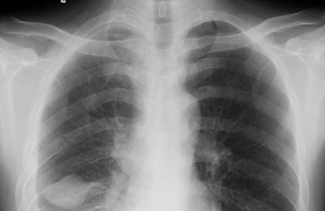

密度: 密度有双重含义,即物质密度和影像密度。物质密度系指单位体积内的物质质量,由物质的组成成分和空间排布情况决定。影像密度则指照片上模拟影像的黑化程度,即对光的吸收程度。又称照片的光学密度或黑化度,简称密度。

天然对比:该概念起源于传统放射学。指X线照片上,人体组织的模拟影像固有的、肉眼可分辨的光学密度差别。

影像对比度:包括两层含义,一是指照片显示的模拟影像上相邻两点间的光学密度的差别,即照片对比度;二是侠义的影像对比度,系指去处光学对比因素,仅反映物体成分的对比度。在传统放射诊断学领域相当于X线对比度。